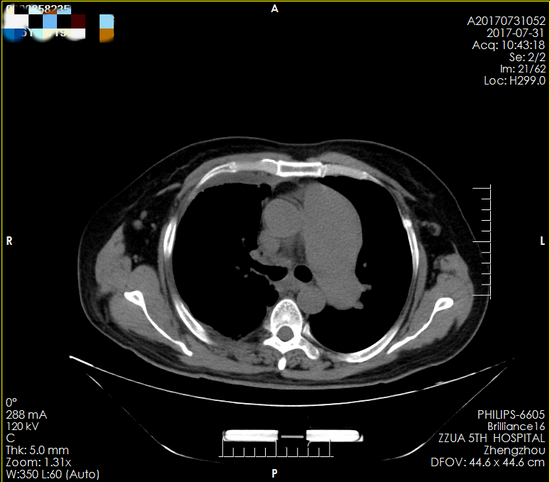

正所谓天无绝人之路,通过亲戚朋友介绍,霍先生的妻子打听到郑州大学五附院心胸外科对处理危重胸外伤有丰富的经验,便抱着试一试的态度连夜转到郑州大学五附院。住院后在高兴才主任指导下,患者的病情一度得到控制,入院后的一周后患者多次突然出现胸闷、气促、呼吸困难,心电监护示:心率110次/分,氧饱和60%左右。值班医师陈涛马上安排急诊床旁胸片检查,结果显示:右肺未见肺纹理(图一),出现了临床上可怕的“大白肺”,在与冯光强副主任医师商议后,考虑患者痰栓阻塞气管引起右肺实变,病情危重。与患者家属沟通后,把霍先生转入呼吸重症监护室,予以气管插管,同时呼吸机辅助正压通气,待情况稳定后行气管镜发现,右主支气管狭窄,气管镜不能通过。复查胸部CT(图二)也证实了气管狭窄的存在。

▲ 图二(箭头所示为气管狭窄)